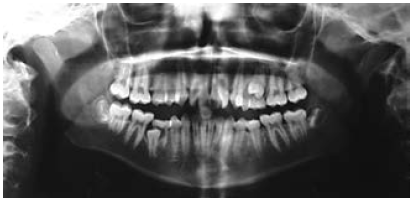

Figure 20. Panoramic image.

Figure 20

Panoramic radiograph: The panoramic radiograph (Figure 20) is a composite radiograph of the teeth and jaws to look for the normal number of teeth, third molars, missing teeth, impacted teeth or supernumerary teeth. This radiographic image also shows bone support and root length.